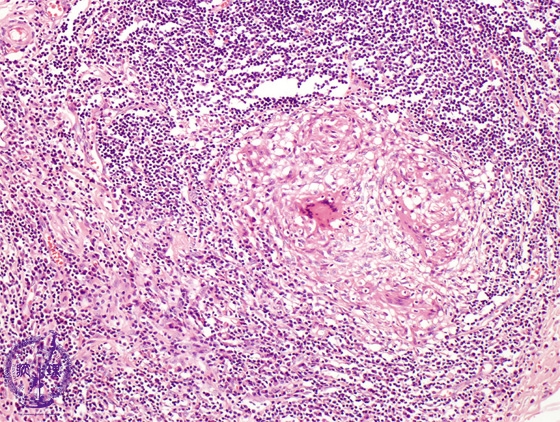

- (5)Intestinal tuberculosis

Microscopic view (H&E stain, high power): Epithelioid granulomas are composed of Langhans type giant cells (arrow).